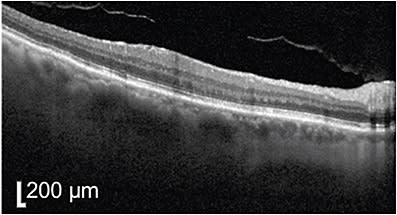

At 1 month, sub-photoreceptor excrescences began to appear (Figure 3), which is, in my experience, a poor prognostic factor for visual outcomes following resolution. The vision had decreased slightly to 20/25, and the patient was notably anxious about the worsening vision and fluid. PDT was performed to an area of 1700 µm with 15 mg of verteporfin. At 6-week follow-up, the patient described complete resolution of his metamorphopsia left eye but his vision remained at 20/25. Drusenoid changes persisted subfoveally (Figure 4).